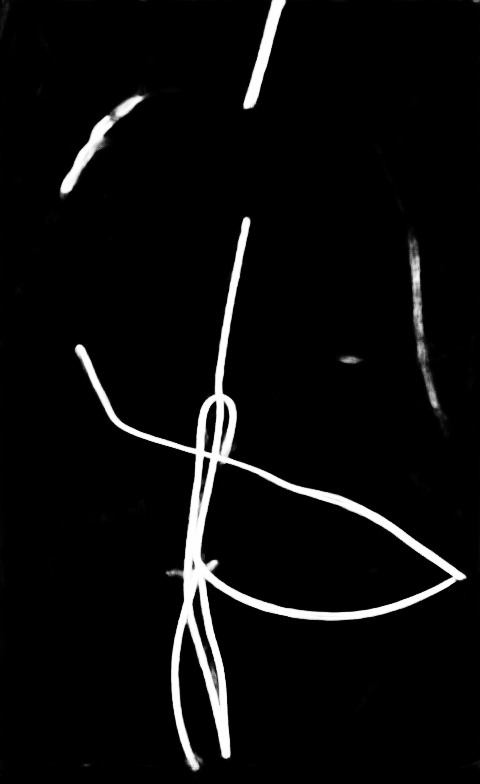

Qualitative visual examples of the raw catheter likelihood maps obtained directly from the network without any postprocessing are shown in Figure 5. It can be seen that the proposed network at the highest scale (scale 3) achieves the best visual appearance as compared to the other methods. The maps from the proposed network at scale 2 and scale 3 look much cleaner than w/oR and fcn8s. We would attribute this to the iterative refinement of the detection results by using the recurrent module. When comparing results from the proposed network at different scales, we can see that the likelihood map from the smallest scale contains almost all line-like structures, including not only catheters but also ribs and ECG leads. This is because catheters, ribs, ECG leads look similar at a smaller scale. These irrelevant line-like structures are gradually filtered out in higher scales because catheters, especially UVCs and UACs, begin to appear as two parallel edges whereas ribs and ECG leads continue to appear as a single solid line.